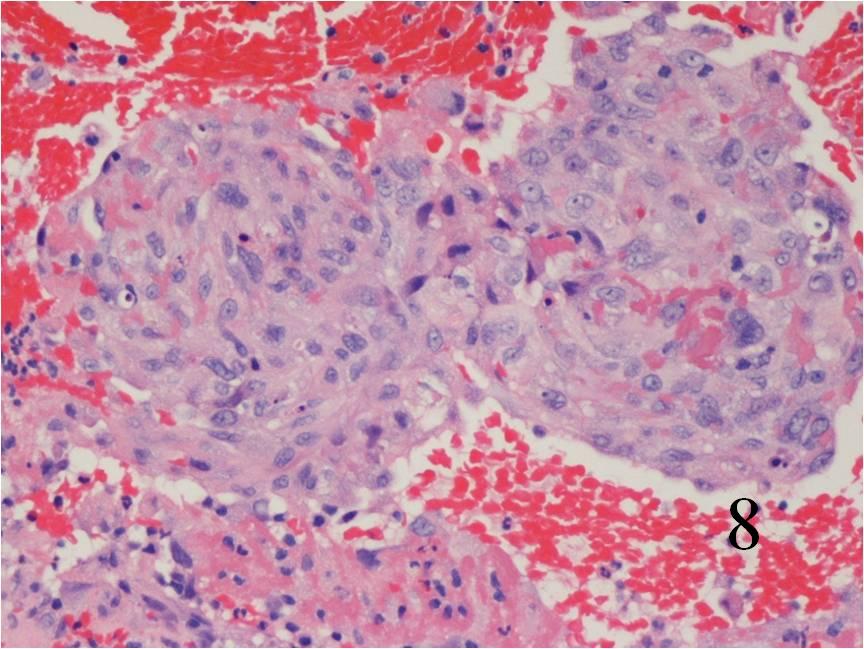

Fig. 8

Fig. 7-8: Microscopic: Low (Fig. 7) and high (Fig. 8) power histology of an angiosarcoma shows abundant round to polygonal tumor cells. Fig. 8 shows nuclear atypia with mitotic activity. The cells are large with large irregular nuclei and significant pleomorphism. The cells appear somewhat epithelioid. The tumor stains positive for vimentin, Factor VIII and CD 34 (not shown in these photographs)